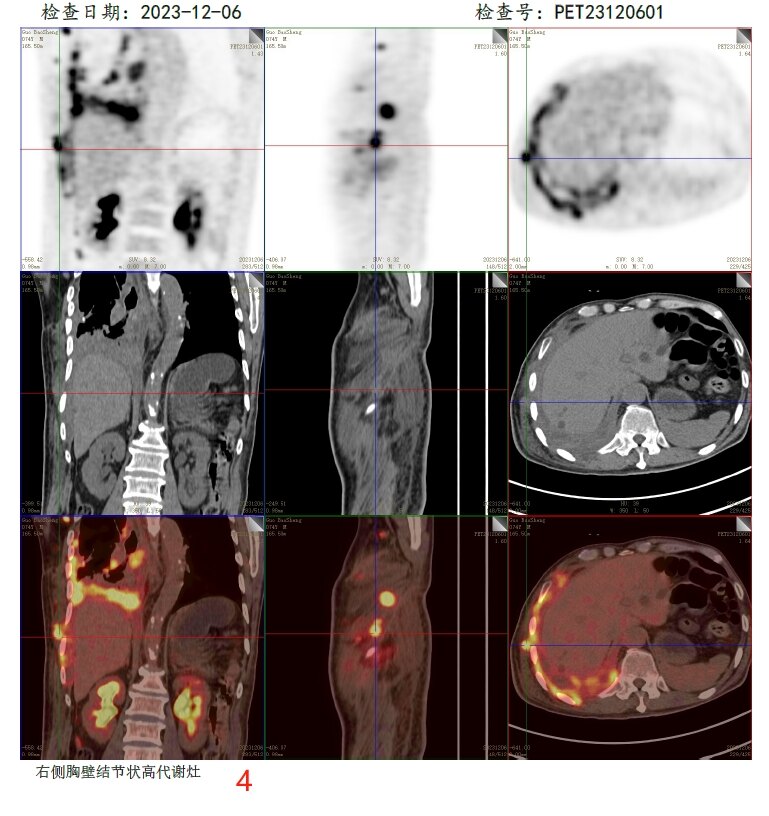

放疗前PET/CT(2023-12-06):

病变层面:

4